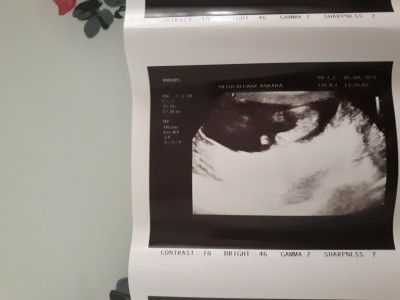

ortadaki çıkıntı sivri şey doktorumuz erkek dedi:) 14 haftalığız değişmez dimi çok net gösterdi kendini kordon böyle durur mu bilen annelere soruyorum teşekkürler

Gebelik haftası 14+2

postun kapanmış burdan atttim canım bak gayet net gözüküyor